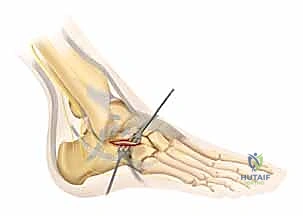

للحفاظ على حيوية الأنسجة الرقيقة (السديلة الجلدية)، يستخدم الدكتور هطيف أسلاك كيرشنر (K-wires) لرفع الجلد بعيداً عن مجال الرؤية دون استخدام مبعدات قاسية قد تدمر الأنسجة. هذه التقنية المتقدمة هي سر التئام الجروح السريع بدون نخر (Necrosis).

3. كشف الكسر وإعادة البناء (Reduction)

بمجرد كشف العظم، يتم تنظيف التجمع الدموي. يقوم الجراح بكشف السطح المفصلي المكسور. باستخدام أدوات دقيقة، يتم رفع الشظايا العظمية المنخسفة إلى مكانها التشريحي الأصلي. يتم استعادة ارتفاع وعرض العظم، والأهم من ذلك، استعادة السلاسة التامة لسطح المفصل.

4. التثبيت المؤقت

يتم استخدام أسلاك معدنية دقيقة لتثبيت الشظايا في مكانها مؤقتاً، ثم يتم التحقق من دقة الرد باستخدام جهاز الأشعة السينية داخل غرفة العمليات (C-arm) لضمان عدم وجود أي انزياح ولو بمليمتر واحد.